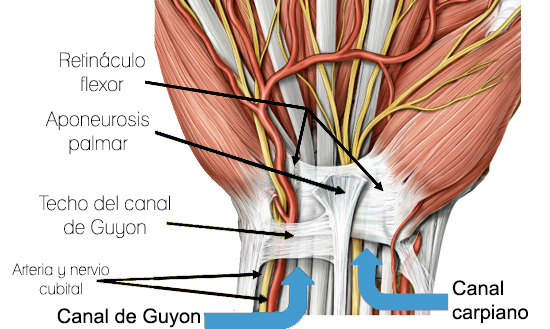

Síndrome de Guyon

El canal de Guyon es un espacio en la muñeca entre el hueso pisiforme y el hueso ganchudo a través del cual la arteria cubital y el recorrido del nervio cubital en la mano. La compresión del nervio cubital se produce en este espacio en la base de la palma. Es comúnmente causado por la flexión repetitiva de la muñeca o la presión excesiva en la palma de la mano. Se caracteriza por dolor, debilidad, entumecimiento, hormigueo y ardor en los dedos meñique y anular.